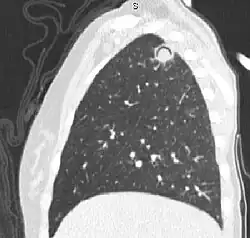

Sagittal reformat from a CT scan of the chest showing air crescent sign in a patient with invasive fungal infection. There is a rounded cavity in the apical right upper lobe, with a non-dependant soft-tissue nodule within it. Also there is some subtle ground-glass opacity surrounding the lesion.

The arrows denote an ill-defined nodular opacity in medial aspect of right upper lobe with ill-defined rim of lucency surrounding it